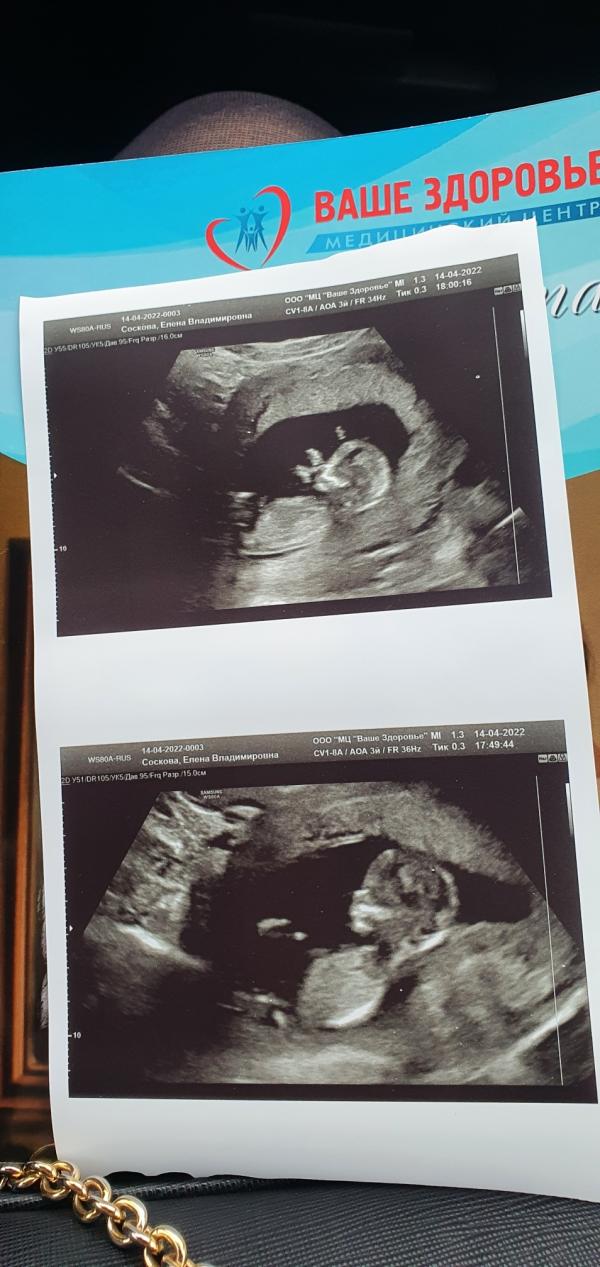

Первый скрининг: ура, у нас будет девочка! Фото малышки на 13 неделе, как прошло УЗИ?

Наш первый скрининг )

ура , у нас будет девочка)

на фото малышке 13 недель . На узи ребёнок и 2с на месте спокойно не лежал)